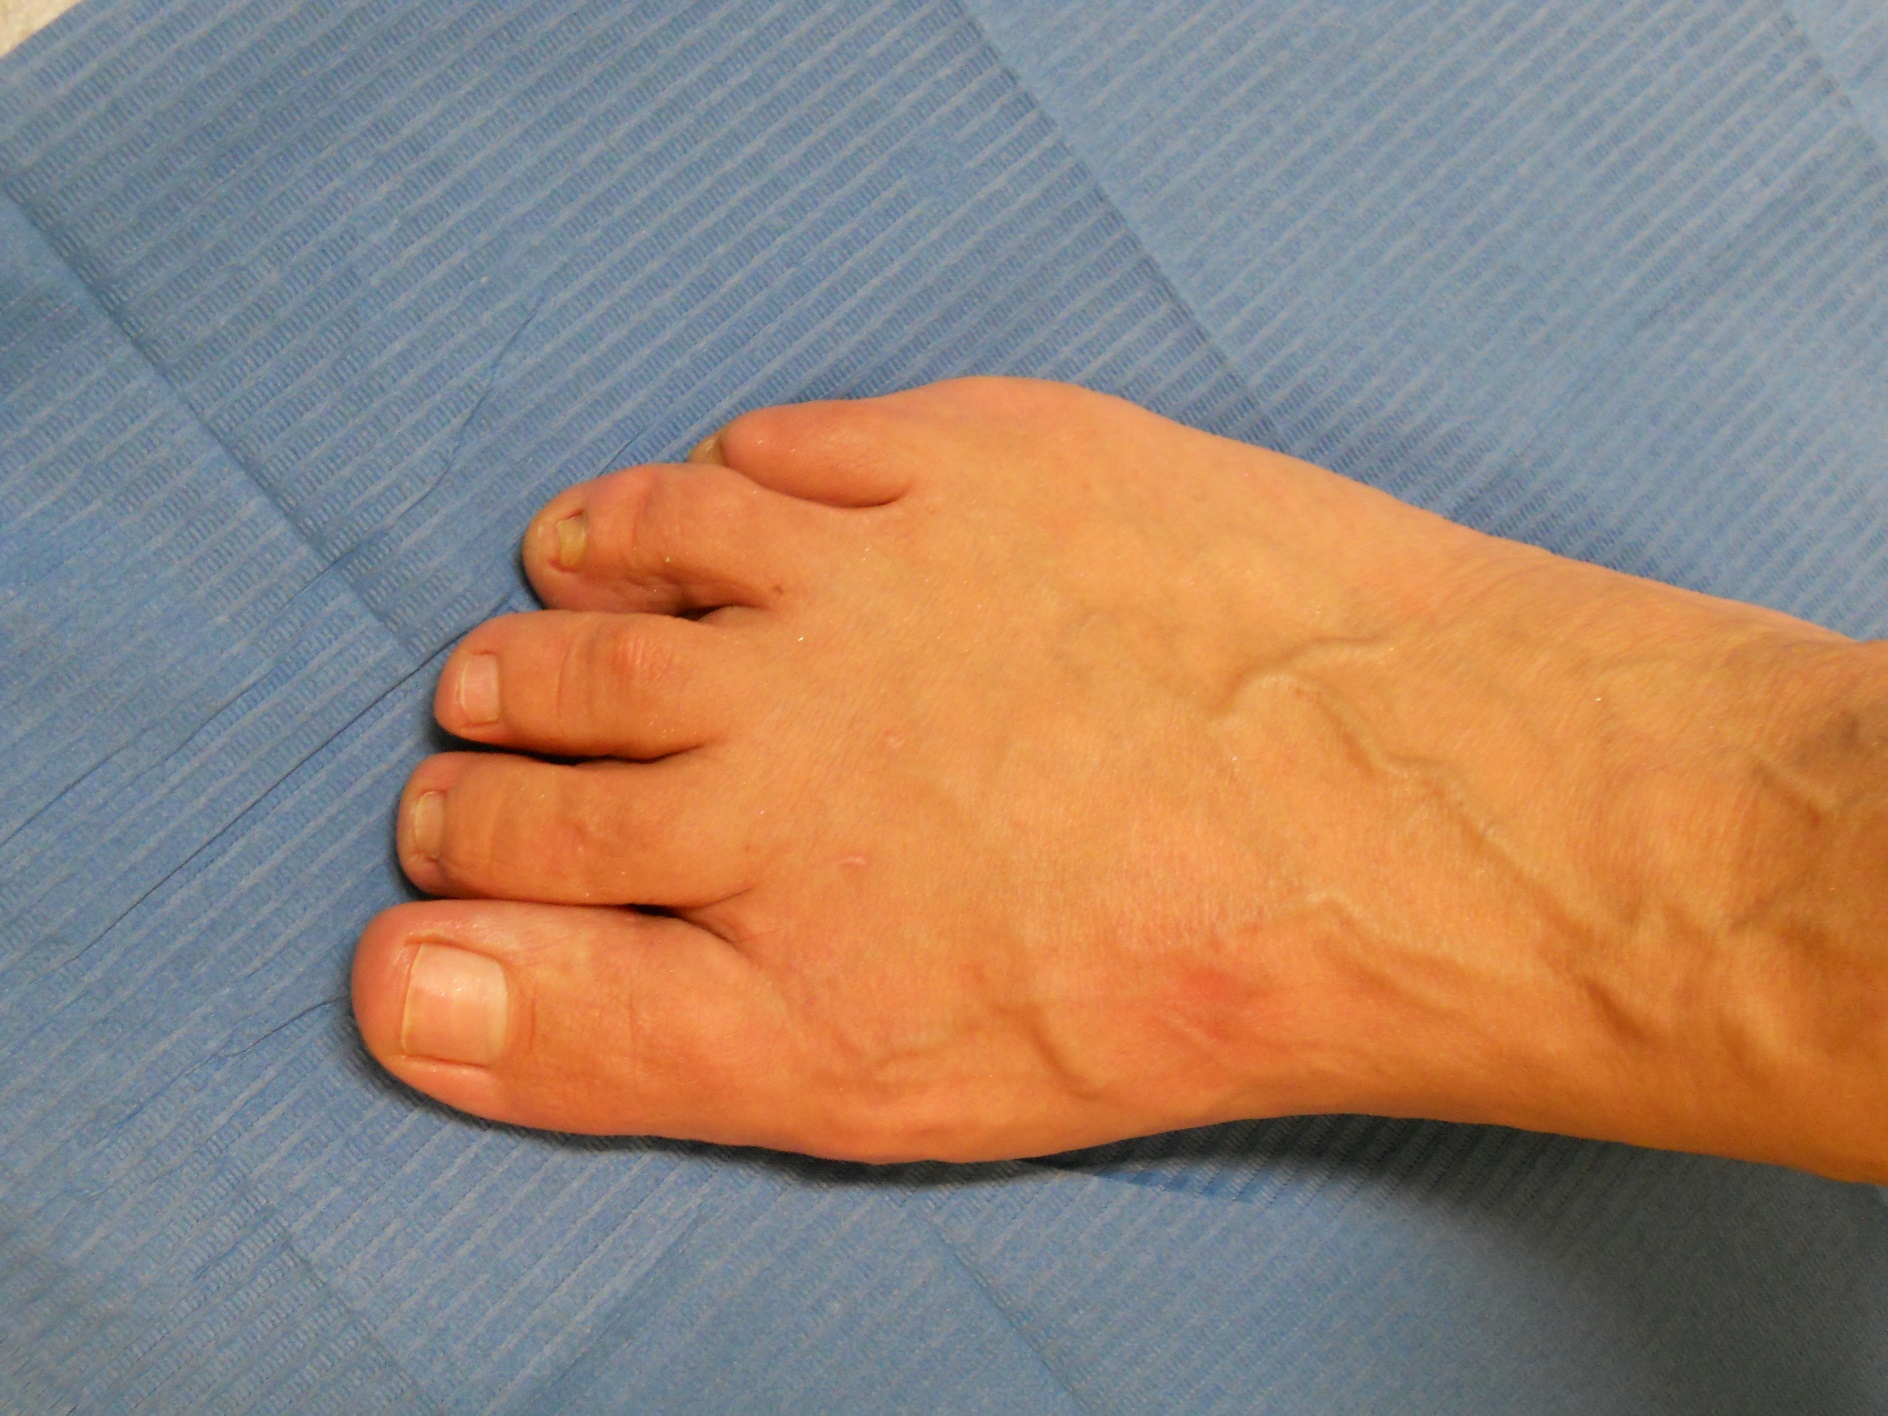

Hallux Valgus (juanete)

Hallux valgus: antes Hallux valgus: después